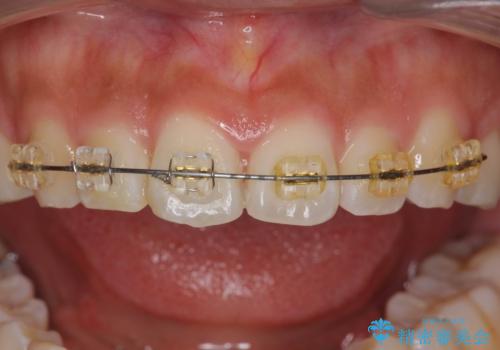

- 前歯の目立つねじれを矯正治療で治したい、と来院されました。

マウスピース矯正を始める前に、ねじれを取るのが短期間で済む部分ワイヤー小矯正を行うことで、全体的な治療期間を短くする治療計画を実行していきます。

前歯のねじれはマウスピース矯正の苦手な動きになり、治療期間が長くなる原因になりやすいです。